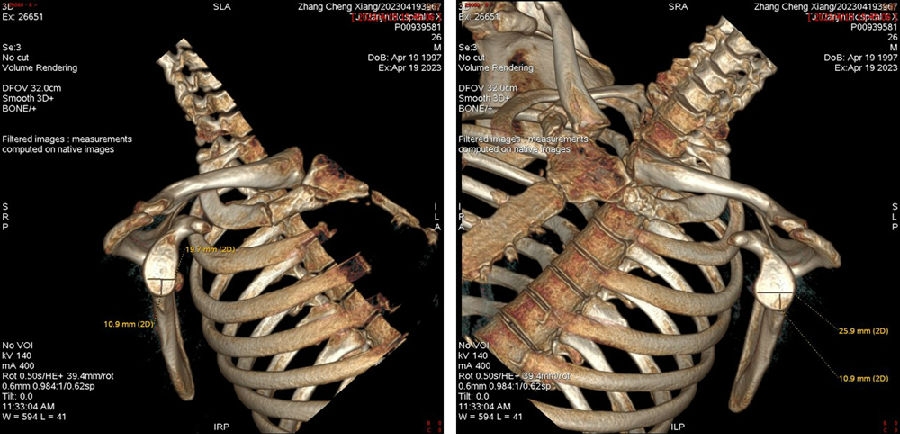

双侧CT三维扫描显示:D=34mm,d=3mm,d/D=肩胛盂骨缺损9%;GT=25.2mm,HIS=30mm。

该患者为轨迹外Hill-Sachs损伤,需要做bankart修补,同时轨迹外做remplissage手术。

图45 CT D=26mm d=8mm(上患侧,下健侧)

图46 CT d/D=30.7% GT=0.83D-d=13.6mm Hill-Sachs损伤I级,骨缺损 >25%